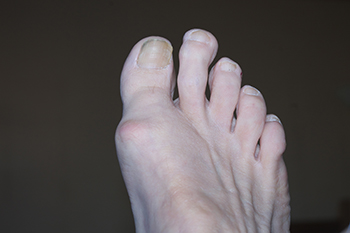

Do You Suffer From Painful Feet?

Do You Suffer From Painful Feet?Painful deformities, such as hammertoes, can be treated. Stop living with foot pain, and have beautiful feet again! The information provided in this article is not meant to be medical advice and is for educational purposes only. If you...

Common Foot Surgeries

Common Foot SurgeriesFoot pain can often be attributed to a number of conditions, including bunions, hammertoe, metatarsalgia, and neuromas, that require surgical intervention. Bunions are painful bony bumps on the side of the foot, caused by misalignment of the toe...